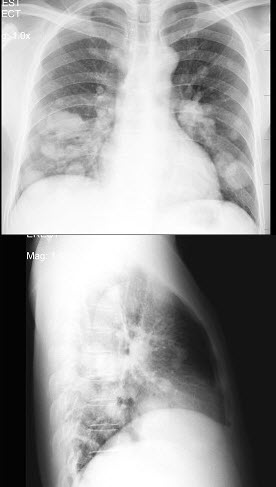

43、单项选择题

男,36岁,半年前痰中带血,发现有肺癌,近几天感胸痛、咳嗽,X线检查如图,最可能的诊断是()

A.血行播散型肺结核

B.细支气管肺泡癌

C.肺转移瘤

D.正常胸片